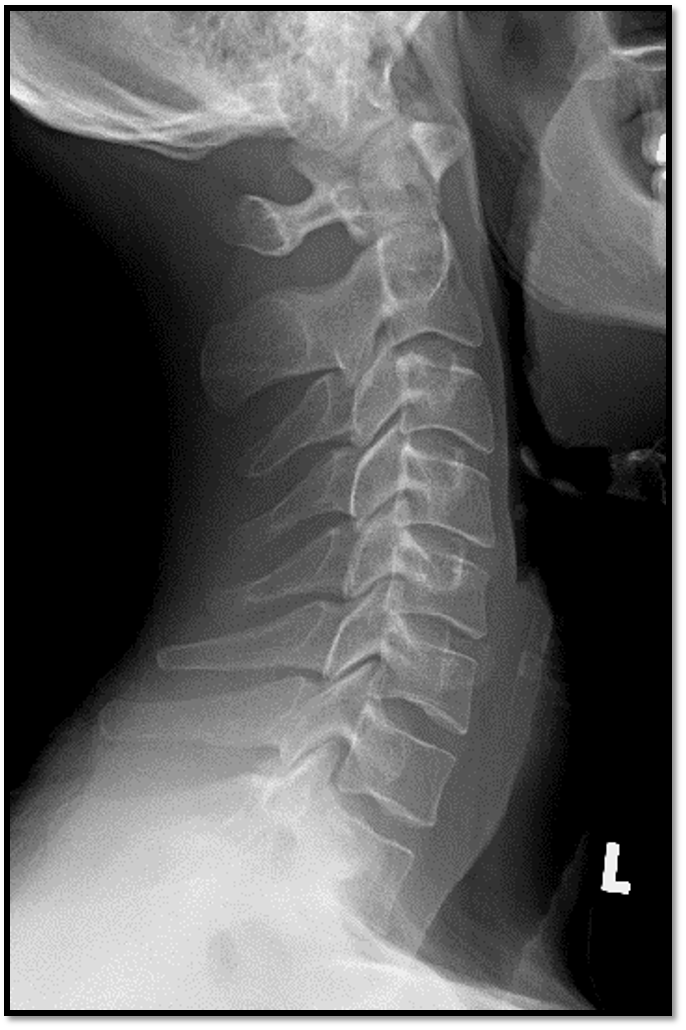

4

Q

A

• chin on mandible

• rotation and tilt

• would need swimmers or more relaxed shoulders